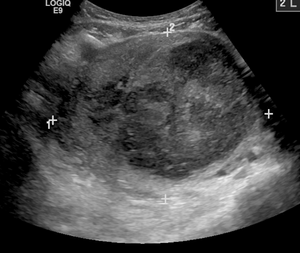

Also common to all intervention radiology procedures are the medical imaging machines that allow the healthcare provider to see what is occurring within the body. Some use X-rays (such as CT and fluoroscopy) and some do not (such as ultrasound and MRI).[2] In each case, the images created may be modified by computer to better visualize the structures as is in the case with digital subtraction angiography, CT and MRI, or the display of the images improved with virtual reality or augmented reality[3] presentation.[4]

- Fine-needle aspiration: obtaining cells from a tissue or organ under ultrasound guidance.